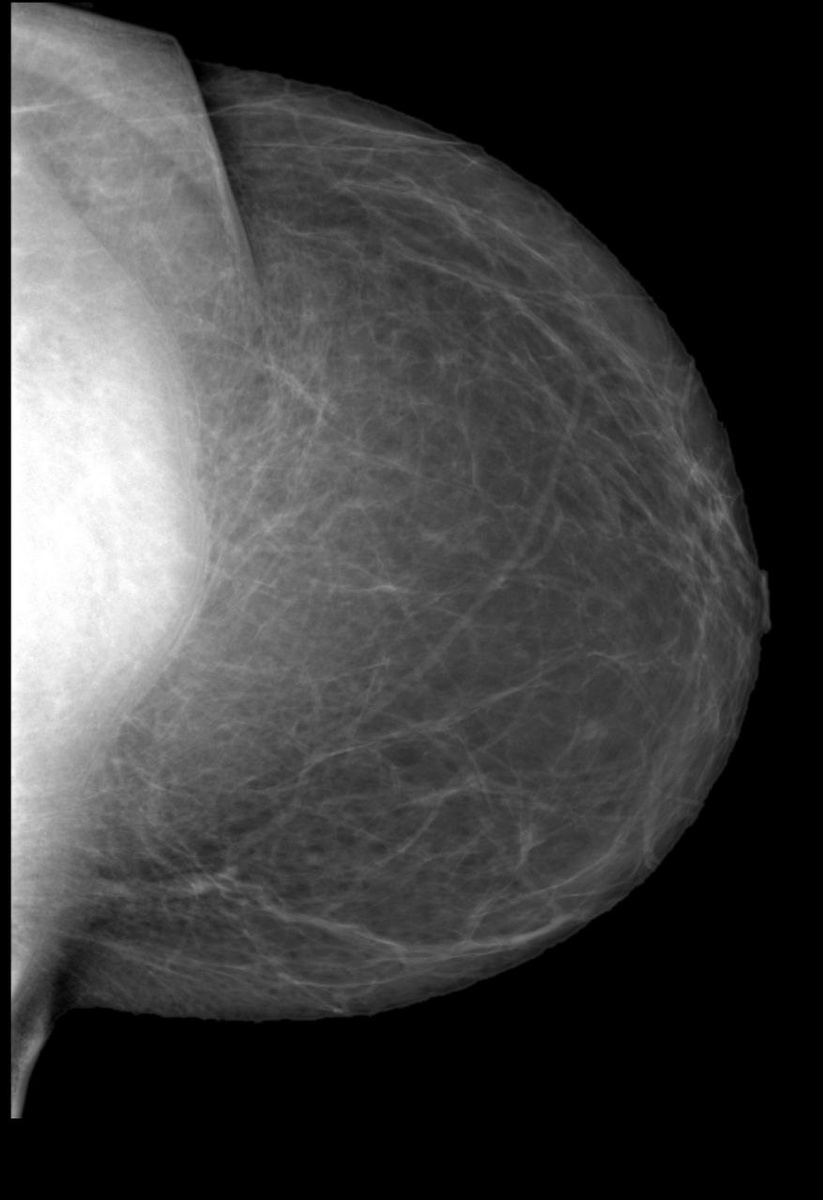

Диагностика филлоидной опухоли

Маммография в сочетании с УЗИ при необходимости дополняется МРТ.